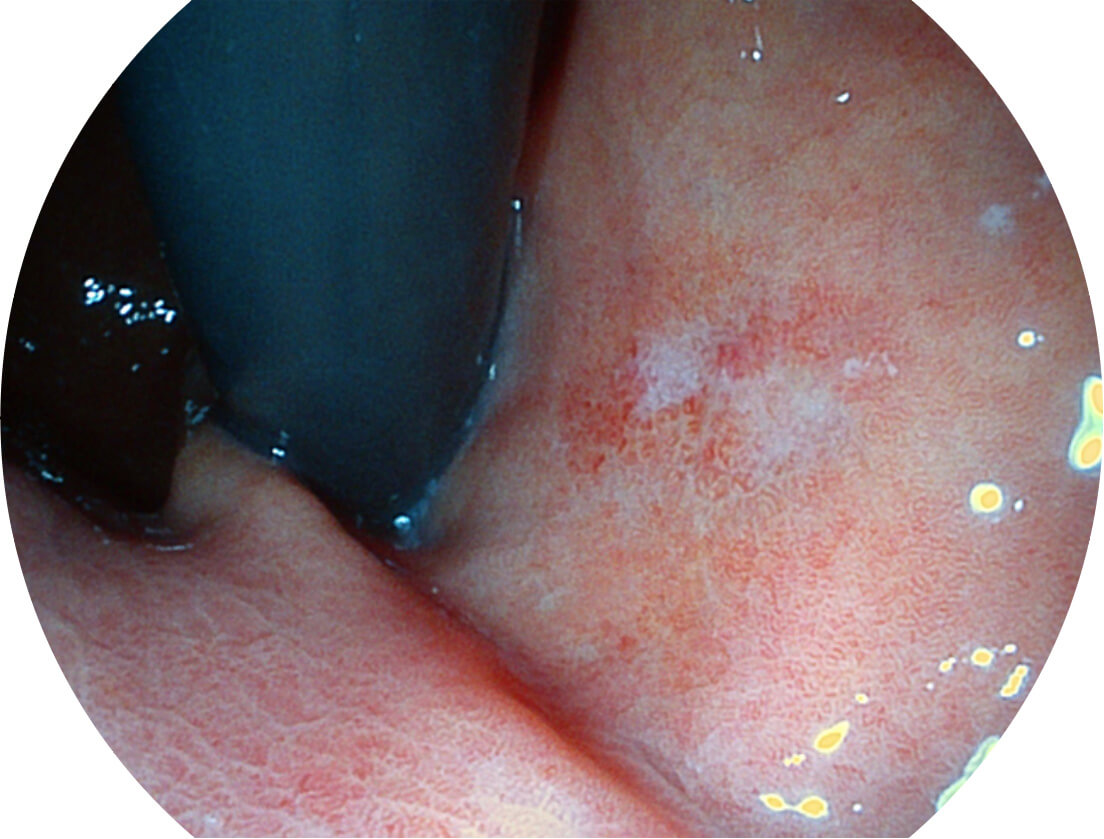

图像具有高亮度、高黏膜血管颜色对比度的特点,且不改变粘液、食物残渣、粪便的基本颜色,可在中远景下进行观察,助力消化道早期疾病的诊断。

SFI图像